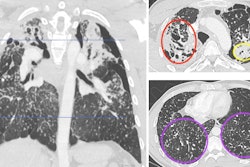

12-year-old male patient who underwent chest CT due to hepatocellular carcinoma. Cropped axial CT images in pediatric patient showing CAD results operating at mean of two false positives per scan for both standard-dose and low-dose scans. Red contours represent FlyerScan CAD system detections. Cyan boxes represent MONAI CAD system detections. Blue "+" symbols represent annotated nodule center-of-mass coordinates, determining reference standard. (Left) Standard-dose image (1.39 mSv). Both CAD systems identified nodule. (Right) Low-dose image (0.34 mSv). Nodule was identified by FlyerScan but missed by MONAI. Images and caption courtesy of the AJR.

Lower CAD system performance is likely due to differences in CT exam dose, the group explained, noting that "greater image noise associated with a lower dose may obscure subtle nodule characteristics that would otherwise help to distinguish the nodule from normal vasculature."